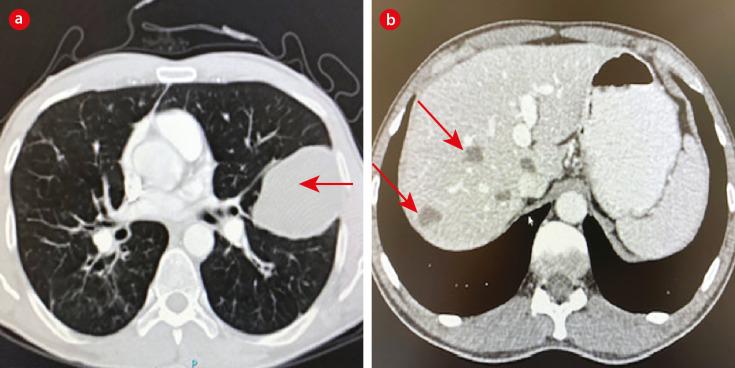

Over a 12-year period we saw nine cases of hydatid disease; two cases in females and seven cases in males. The median age of our patients was 31 years old. Four patients had pulmonary cysts, four had hepatic cysts, and one patient had pulmonary and hepatic cysts. The majority of patients were from the Ad Dakhiliyah governorate. Contact with animals was reported by three patients, denied by two, and unknown for four. Albendazole was prescribed to three patients with pulmonary cysts that subsequently ruptured reflecting the unfamiliarity of clinicians to best manage pulmonary hydatid cysts.

在12年期间,我们共诊治了9例包虫病病例;其中女性2例,男性7例。患者的中位年龄为31岁。4例患者有肺囊肿,4例有肝囊肿,1例患者既有肺囊肿又有肝囊肿。大多数患者来自达希利耶省。3例患者报告与动物有接触,2例否认,4例情况不明。3例肺囊肿患者使用了阿苯达唑,随后囊肿破裂,这反映出临床医生对肺包虫囊肿的最佳管理并不熟悉。